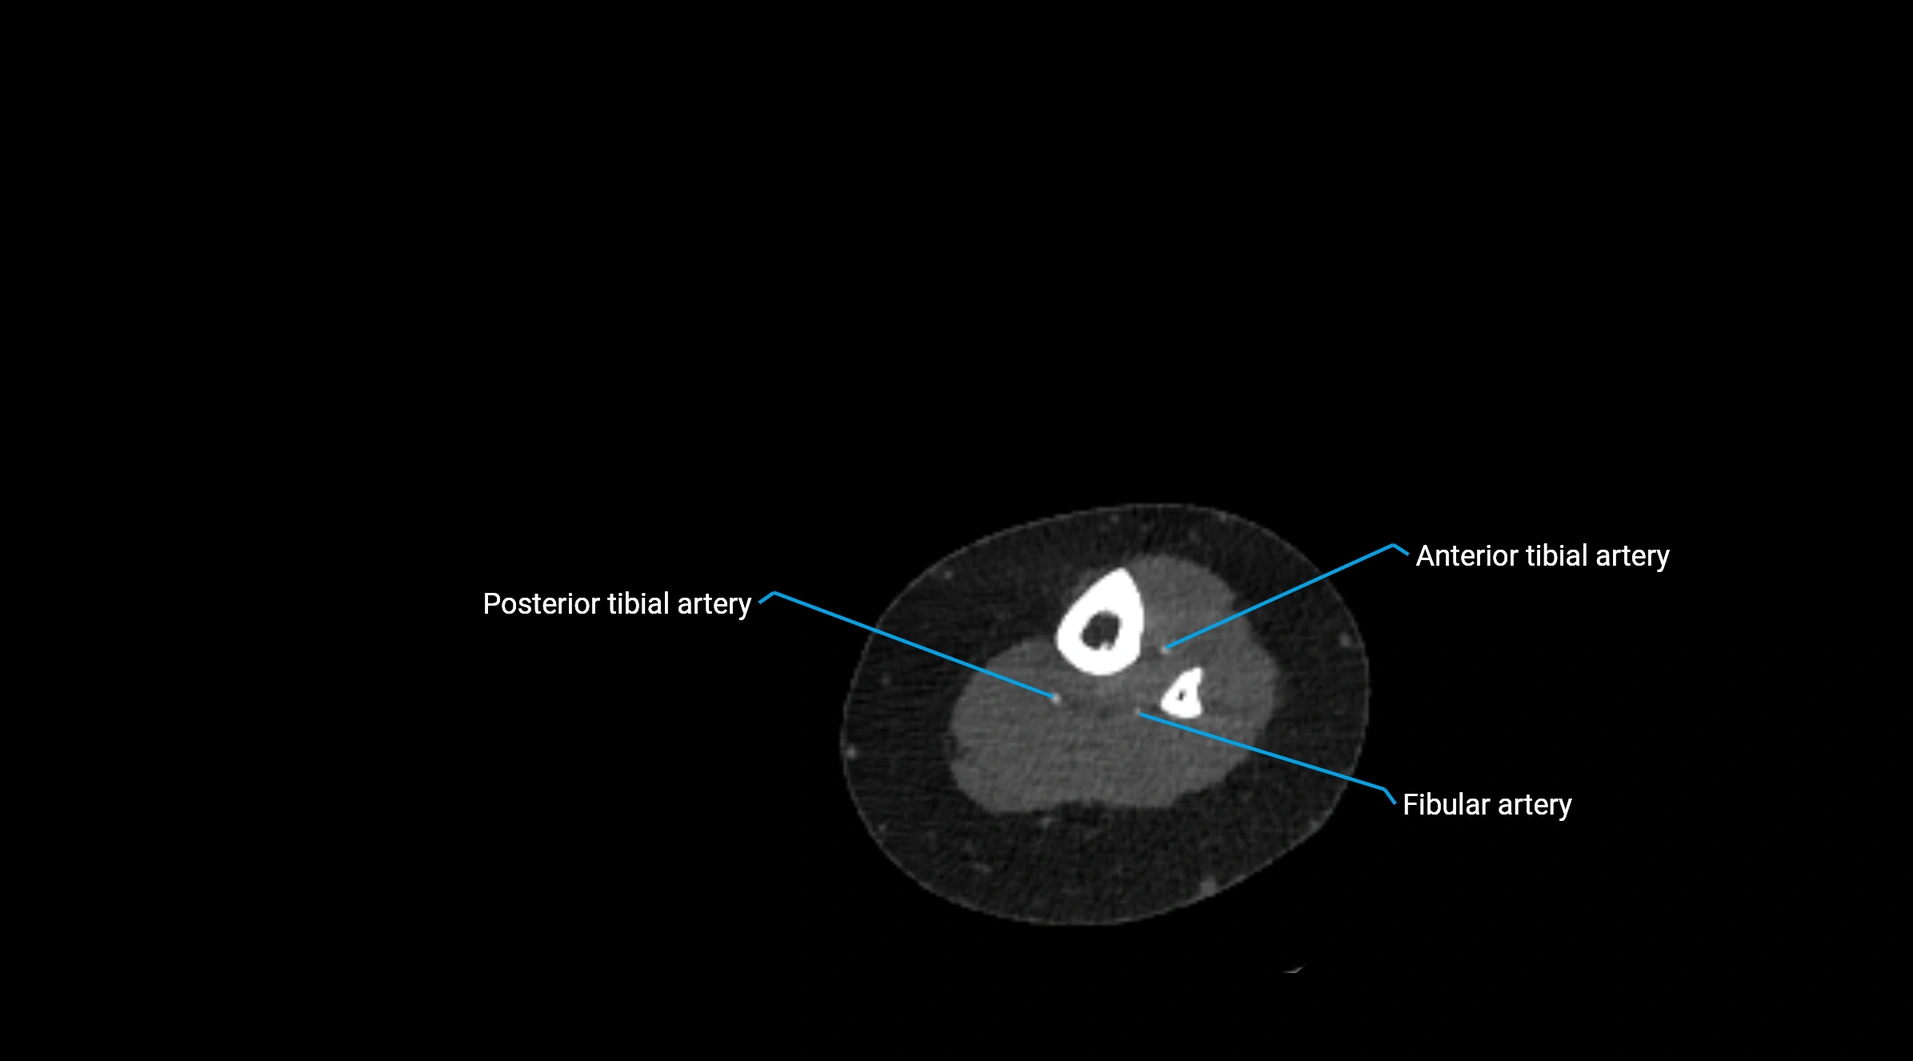

CT images

image